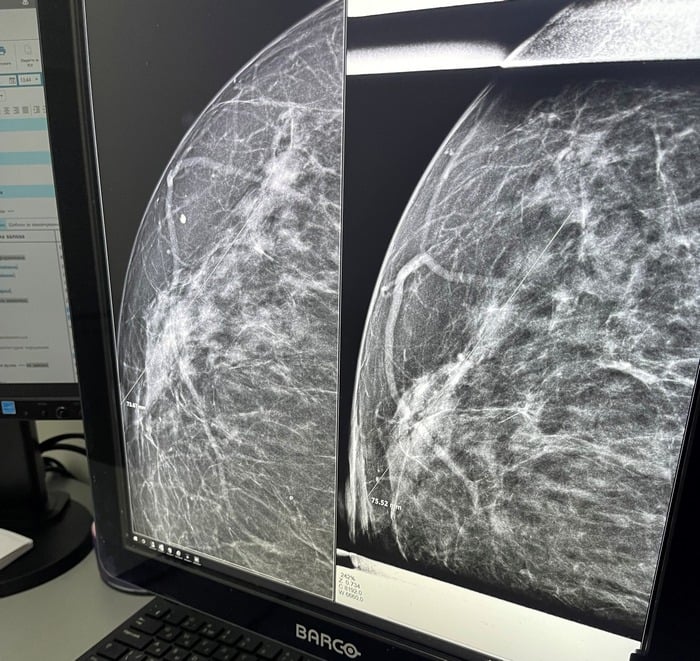

Самая большая опасность для груди - отсутствие контроля над ее здоровьем. Без самообследований раз в месяц в домашних условиях и ежегодного посещения маммолога невозможно узнать о наличии многих заболеваний молочных желез на их ранних стадиях развития, поскольку чаще всего они бессимптомны. Так, в отличие от мастита, который сразу проявляется болью, покраснением, лихорадкой, рак груди может месяцами никак не давать о себе знать. Хотя с помощью УЗИ или маммографии он уже может быть выявлен.